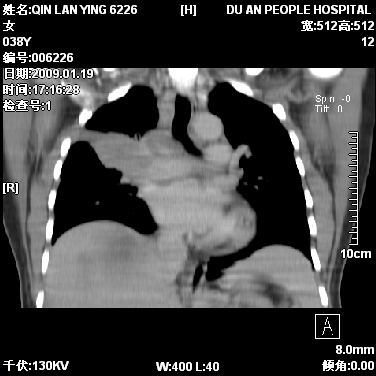

标题: CT17781:女,38岁,胸疼1个月。

女,38岁,胸疼1个月。wbc:1万4

1)右肺中央型肺癌并右肺上叶阻塞性肺炎、节段性肺不张,纵隔淋巴结转移、右侧胸膜转移、肝脏转移。2)右侧胸腔少量积液。

1、右侧中央型肺癌并阻塞性肺不张,纵隔内、主动脉弓旁、右肺门淋巴结及肝脏转移可能性大,建议纤支镜进一步检查。

2、右侧胸腔积液。

本病例有几个容易诊断的地方:1、右肺上叶前段支气管闭塞,肺不张。2、淋巴结明显肿大。3、肝脏多个类圆形低密度影呈“牛眼征”改变,高度提示转移。

从影像学角度分析      右肺上叶中央型肺癌,并阻塞性不张、肺炎,纵隔淋巴结、膈顶淋巴结转移。